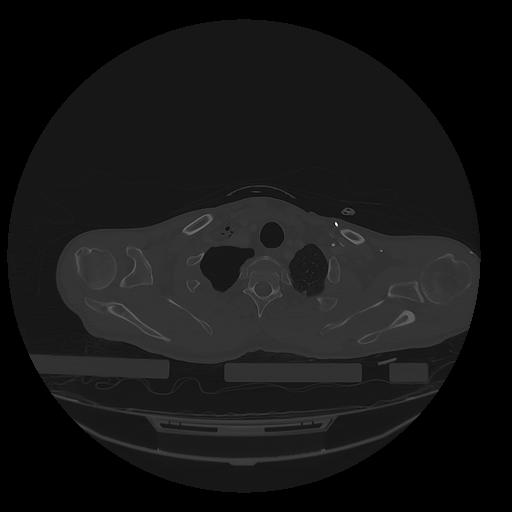

31 PULMON,CE,Vol,1.0,PULMON,,